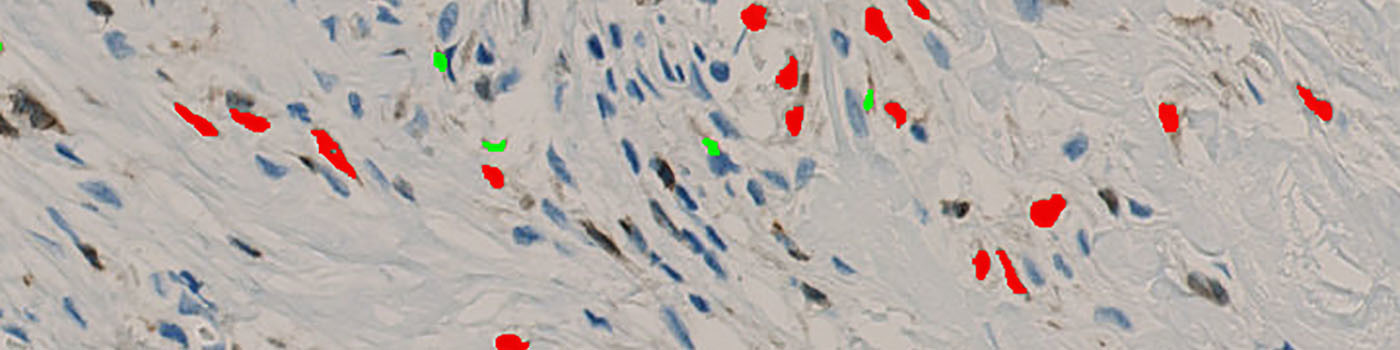

The first image processing step involves a segmentation of background, tissue, negative and 5LO positive nuclei (see FIGURE 3). Next a post-processing step is applied to remove background, tissue and negative nuclei (see FIGURE 4). Additionally, 5LO positive nuclei are separated into two groups based on their area (below and above 10 µm2) and nuclei with a too low staining intensity are removed. The image obtained after post-processing (see FIGURE 5) is used to determine the output variables.

Segmented nuclei are categorized in nuclei of area above and below 10 µm2. The output variables of the protocol include measurements from the two groups of nuclei and a total of these: